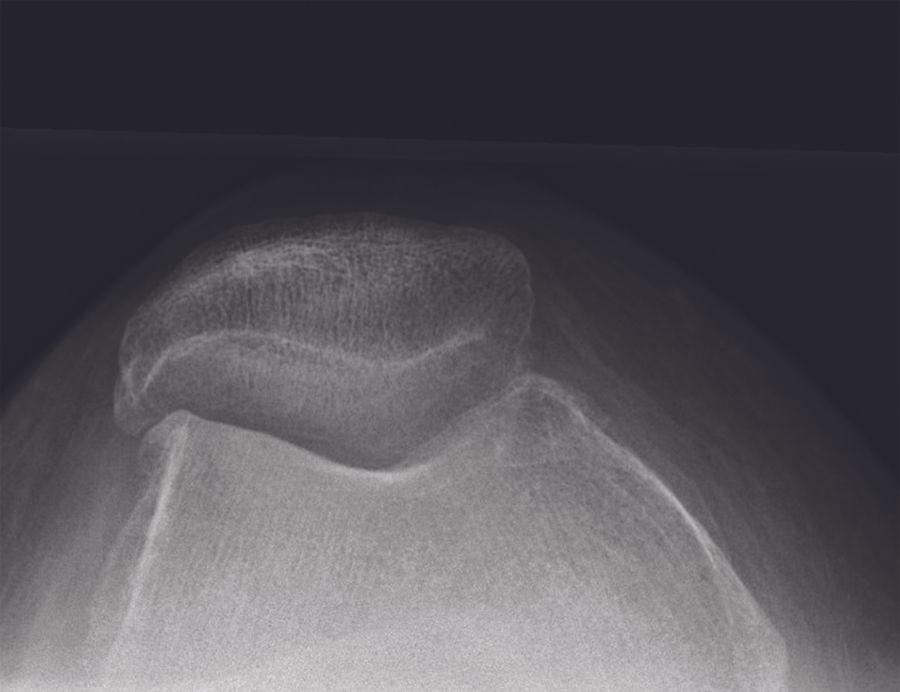

Radiographic assessment (fig. 1A-C)

My routine radiographic examinations of patients referred with pain believed to origin from knee OA include weight-bearing AP, lateral, and skyline views. These may be supplemented by valgus and varus stress radiographs, a Rosenberg view and / or MRI of the knee as needed. It is fundamental to establish bone-on-bone OA in the lateral compartment. Due to the specific features of lateral compartment OA bone-on-bone may not present on the weight-bearing radiograph with the knee extended. If there is any doubt about the bone-on-bone diagnosis in the lateral compartment supplemental imaging should be applied. On the weight-bearing AP view it is also assessed if there is preserved cartilage in the medial compartment. If in doubt a varus-stress radiograph may be helpful to assess this, and at the same time a varus stress will show correction of valgus deformity, opening of the lateral compartment, and indirectly that the LCL is functionally intact. In the lateral radiographic view the relative position of the femur and tibia should be assessed. If the femur is very posteriorly positioned it may be a sign that the ACL is degenerative and torn. The skyline view is specifically assessed for the presence of severe bone-on –bone OA. In general I only find MRI examination necessary in younger patients, particularly if the knee hos posttraumatic OA, in which case MRI can give good information about cartilage damage and degeneration in the lateral and the remaining compartments, as well as the status of cruciate ligaments.

- If there is severe patella-femoral OA LUKA should not be performed. Despite the off-loading of the patella-femoral joint resulting from the deformity correction the effect of severe OA is not fully understood.